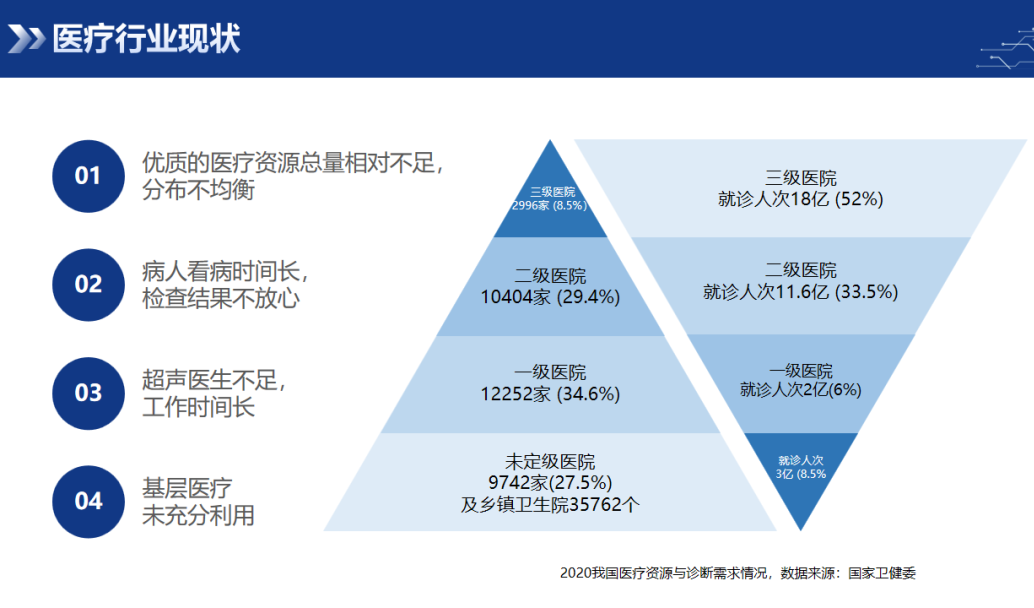

行业背景

随着人口老龄化及社会节奏加快,重大疾病和慢性疾病呈现高发且年轻化趋势,我国社会医疗负担加大,医疗资源的质量和效率亟待提高,亟待有新技术、新产品、新模式改变现状。

超声检查是临床最为普及应用最广泛最频繁的影像学检查方法之一,在多种疾病的临床诊疗中发挥着越来越重要的作用。然而,超声临床还存在五大痛点:

■ 痛点一:超声医师总量不足,我国超声医生缺口超过20万人; |

■ 痛点二:超声医师地域分布不均,资深医师集中在大城市大医院,基层非常缺乏; |

■ 痛点三:超声扫诊模式落后、均质化程度低、结果不互认; |

■ 痛点四:超声医师培养周期长; |

■ 痛点五:医师工作强度大,80%的医师退休后都患有肩周炎、腰椎疼痛等职业病,诊断效能会下降。 |

借助新技术、新产品,如协作机器人进行最大化利用现有超声医师资源,加快提升广大基层的服务水平,进而促进优质医疗资源下沉、医患隔离、减轻医师工作强度,有重要临床、民生和经济价值。